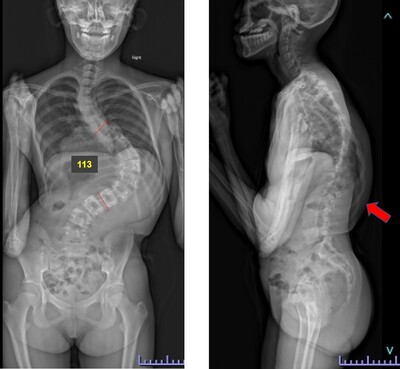

思春期特発性側弯症が高度に進行した症例です。最大側弯角度は113°であり、100°を超える側弯の手術は一般的に神経合併症が危惧されます。神経合併症を極力防ぐため、また侵襲を低減する目的で、同じ入院期間に2回に分けて段階的に矯正手術を行いました。1回目に最も側弯の強い箇所に対して側方から椎体間解離を行い、2回目に後方から全体のバランスが良くなるように慎重に矯正固定術を施行しています。

神経合併症はなく、術後の最大側弯角度は15°に改善(矯正率:87%)、背中の大きなコブも無くなっているのが分かります(赤矢印)。神経合併症が発生しないように慎重に手術を行うのは当然ですが、側弯を治すだけでなく横から見た姿勢を治すことにも留意しています。